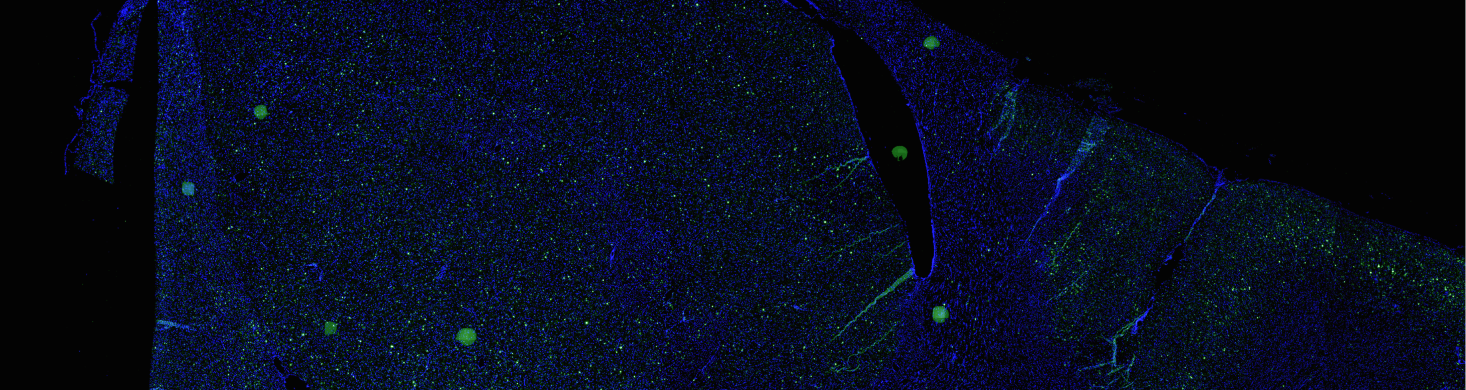

Launched in 2026, the Dyno-yp2 is a top-performing capsid that achieves both exceptional brain transduction and significant liver detargeting in TfR-humanized mice.

Launched in 2025, the Dyno-ahq vector is optimized for widespread IV delivery to the brain, with exceptional liver detargeting and a highly conserved mechanism for blood-brain barrier crossing.

Launched in 2023, the Dyno-hc9 vector (aka bCap 1) was the first Dyno brain capsid optimized for highly efficient pan-brain delivery across the blood-brain barrier, with broad CNS tropism and liver detargeting.